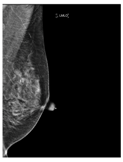

| ACR Class | Feature | Tissues Proportion | Example |

|---|---|---|---|

| D | Extremely dense | More than 75% dense tissue | ![]() |